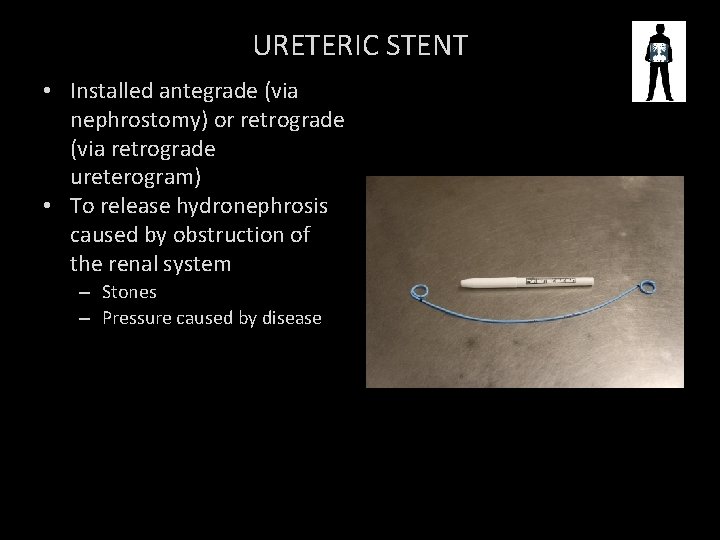

URETERIC STENT • Installed antegrade (via nephrostomy) or retrograde (via retrograde ureterogram) • To release hydronephrosis caused by obstruction of the renal system – Stones – Pressure caused by disease